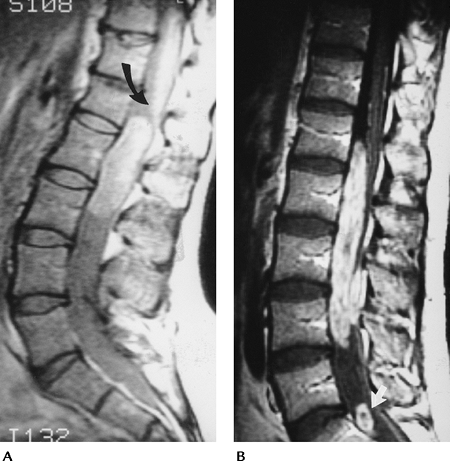

|

FIGURE 3-57 Postoperative lumbar disc space infection and osteomyelitis. (A) Sagittal CT scout image shows rod and pedicle screw instrumentation L3–L5. The L2–L3 endplates (arrow) are indistinct. Sagittal T1-weighted (B) and T2-weighted (C) images demonstrate loss of the endplates (open arrows) and increased signal intensity (white arrow) in the disc on the T2-weighted image (C). Note the minimal metal artifact (black arrows).

FIGURE 3-58 Tuberculous spondylitis in the thoracic spine. Sagittal T1-weighted (A) and T2-weighted (B) images demonstrate disc space loss and vertebral compression with paravertebral soft tissue extension (arrows). Off-axis sagittal image (C) shows a large multiloculated paraspinal abscess.